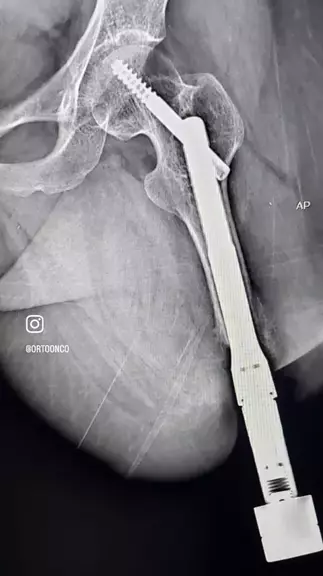

#osseintegration #implante #kwainobrasileirao